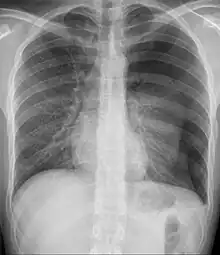

Since most causes of pediatric and adolescent chest pain are not considered life-threatening, parents and their children are often reassured that in the majority of cases, the cause of the pain can be determined. If the child or adolescent appears to have some dehydration, and intravenous line along with administration of saline is done. The clinician may or may not decide to perform diagnostic testing . This is especially true if the child or adolescent has symptoms of chronic pain. If an obvious cause of the chest pain is not readily apparent, testing may begin with an x-ray and an electrocardiogram . This helps the clinician to determine whether or not the cause of pain is related to pulmonary or cardiac causes.[4]